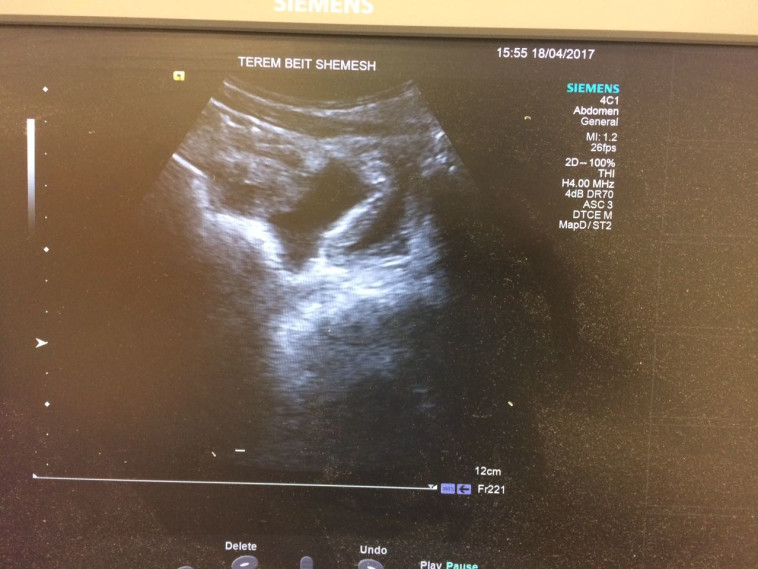

אלא שהילד המשיך להתלונן על כאבים, מה שגרם להוריו לפנות למיון 'טרם'. אנשי הצוות הרפואי במיון 'טרם', בראשות ד"ר זאב ווימפהיימר, ביצעו בדיקות מקיפות ובהם בדיקת אולטרה סאונד, שבה התגלה דימום פנימי בבטנו של הילד.

"האבחון המהיר הציל את חייו של הילד". בדיקת האולטרה סאונד. צילום: מוקד טרם

"האבחון המהיר הציל את חייו של הילד". בדיקת האולטרה סאונד. צילום: מוקד טרם | "האבחון המהיר הציל את חייו של הילד". בדיקת האולטרה סאונד. צילום: מוקד טרם